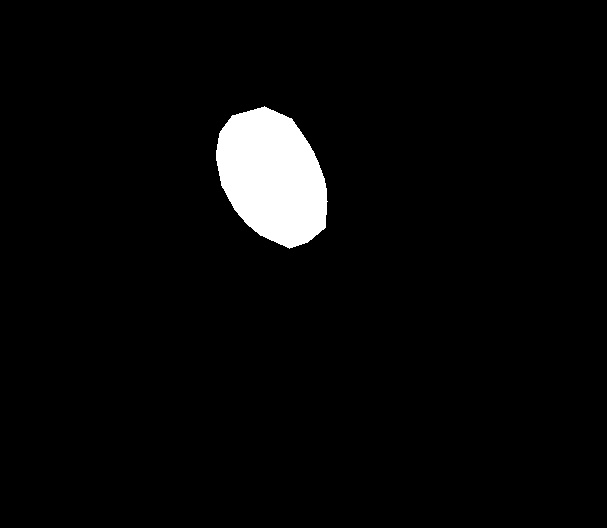

A few sample images and the corresponding masks of the polyp dataset in HyperKvasir are shown in Fig 2. The polyp images are RGB images. The masks of the polyp images are single-channel images with white () for true pixels, which represent polyp regions, and black () for false pixels, which represent clean colon or background regions. In this dataset, there are different sizes of polyps. The distribution of polyp sizes as a percentage of the full image size is presented in the histogram plot in Fig 3, and we can observe that there are more relatively small polyps compared to larger polyps. Additionally, a subset of this dataset was used to prove that the performance of segmentation models trained with small datasets can be improved using our SinGAN-Seg pipeline, and the whole dataset was used to show the effect of using SinGAN-Seg generated synthetic images instead of a large dataset which has enough data to train segmentation models. In this regard, this dataset was used for two purposes:

To understand the difference between the mask distribution of real images and synthetic images, we plotted pixel distribution of masks of synthetic images in Fig 6. This plot is comparable to the pixel distribution presented in Fig 3. The randomness of the generations made differences in the distribution of true pixel percentages compared to the true pixel distribution of real masks of real images. However, the overall shape of synthetic data mask distribution shows a more or less similar distribution pattern to the real true pixel percentage distribution.